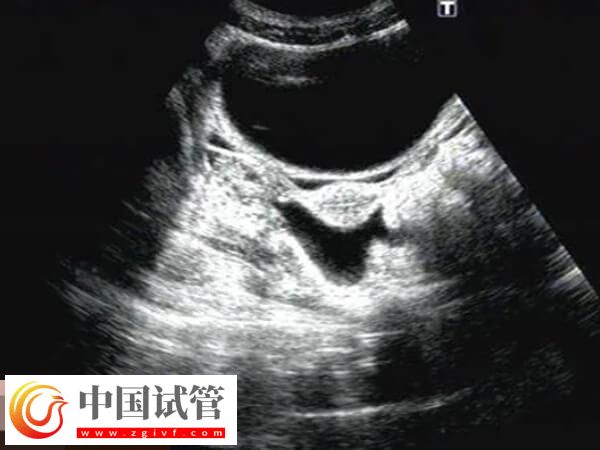

一般女性在试管鲜胚移植40天左右出现宫腔积液的情况较为常见,可能是胚胎植入子宫内膜导致的积液现象,也可能是其它原因,至于出现积液后多久干净,对此感兴趣的可以参考下列内容:

患者在试管鲜胚移植40天检查发现宫腔有积液,若是宫腔积液量较少,主要由生理因素引起的,那么通常不需要进行治疗,会自行消失,一般可能需要7-10天左右能使宫腔积液自行吸收。

试管鲜胚移植40天宫腔有积液,若是因怀孕后体内的黄体功能不足,孕激素水平也比较低,导致的宫腔积液的情况,或是宫腔存在感染现象而出现宫腔积液,那么可能需要1-2个月才能让积液逐步减小或消失。

试管囊胚移植40天宫腔有积液的干净时间不可一概而论,还需要根据实际情况进行判断,毕竟每个患者身体情况不同多样积液消失时间也会有差异,建议出现宫腔积液的患者,应该定期进行超声检查,监测积液的变化,然后根据医生的建议进行适当的保胎措施。